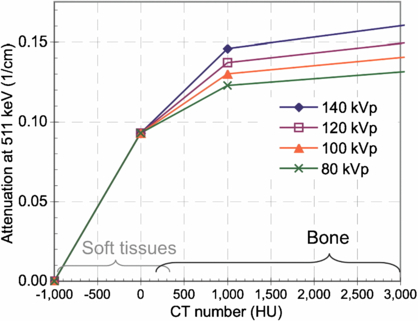

The bi-linear scaling method for PET/CT (Burger et al 2002, Kinahan et al 2003) assumes that all pixels in a CT image with CT numbers between approximately −1000 and 0 Hounsfield units (HU) are a mixture of air and water, while pixels with a CT number greater than 0 HU are composed of a mixture of water and bone. The theory is described in detail elsewhere (Kinahan et al 2003). Our experiments were based on the Discovery STE PET/CT scanner (GE Healthcare, Waukesha, WI), which uses a tri-linear scaling approach. With this method the LAC at 511 keV is estimated by LAC = a × CT + b, where a and b are constants listed in table 1 (conversion factors were determined from internal scanner calibration factors and were derived based on the work by Lonn (2003)) and 'CT' is the CT number in HU. The corresponding conversions are illustrated in figure 1.

Figure 1. Tri-linear scaling method used to convert CT numbers to LACs at 511 keV for different x-ray tube potentials (values provided by the manufacturer). Approximate ranges for CT numbers of soft tissues and osseous tissues are indicated.

Download figure:

Standard imageTable 1. Coefficients used for tri-linear scaling according to LAC = a × CT + b.

| −1000 < CT < 0 | 0 < CT < 1000 | 1000 < CT < 300 00 | ||||

|---|---|---|---|---|---|---|

| Tube potential (kVp) | a (cm−1-HU) | b (cm−1) | a (cm−1-HU) | b (cm−1) | a (cm−1-HU) | b (cm−1) |

| 80 | 9.30e-5 | 0.093 | 3.28e-5 | 0.093 | 4.10e-6 | 0.122 |

| 100 | 9.30e-5 | 0.093 | 4.00e-5 | 0.093 | 5.00e-6 | 0.128 |

| 120 | 9.30e-5 | 0.093 | 4.71e-5 | 0.093 | 5.89e-6 | 0.134 |

| 140 | 9.30e-5 | 0.093 | 5.59e-5 | 0.093 | 6.98e-6 | 0.142 |

Based on figure 8(B), with a typical error in LACCTAC of up to −3.1% at 140 kVp and up to −6.8% at 120 kVp, we would thus expect an SUVMAX error of approximately −3.1% and −6.8% at 140 and 120 kVp. This represents a range for PET/CT imaging parameters on clinical scanners using the tri-linear transform method described above (figure 1 and table 1).

Our results show that the per cent error in PET SUV for bone imaging is roughly proportional to the per cent error in the linear attenuation coefficients estimated from the CT scan (LACCTAC). The errors in bone LACCTAC in turn ranged from −1.3% to −6.8% at 140 and 120 kVp, depending on the experiment and type of analysis performed. Thus we expect the error to be between −1.3% and −6.8% for PET tracer uptake values in bone lesions over a wide range of SUVs, with smaller errors for the higher kVp scans. Errors increased for cortical bone as the scan kVp was reduced. While errors in estimated PET tracer values most likely do not influence clinical interpretation, quantitative studies evaluating therapeutic response in bone should account for changes in bone composition. These results will apply to all PET tracers and are based on the specific tri-linear scaling method implemented in the PET/CT scanner we used for the experimental studies (figure 1 and table 1). On other PET/CT scanners there are variations in how the scaling method is implemented. For those systems these results should be re-evaluated.